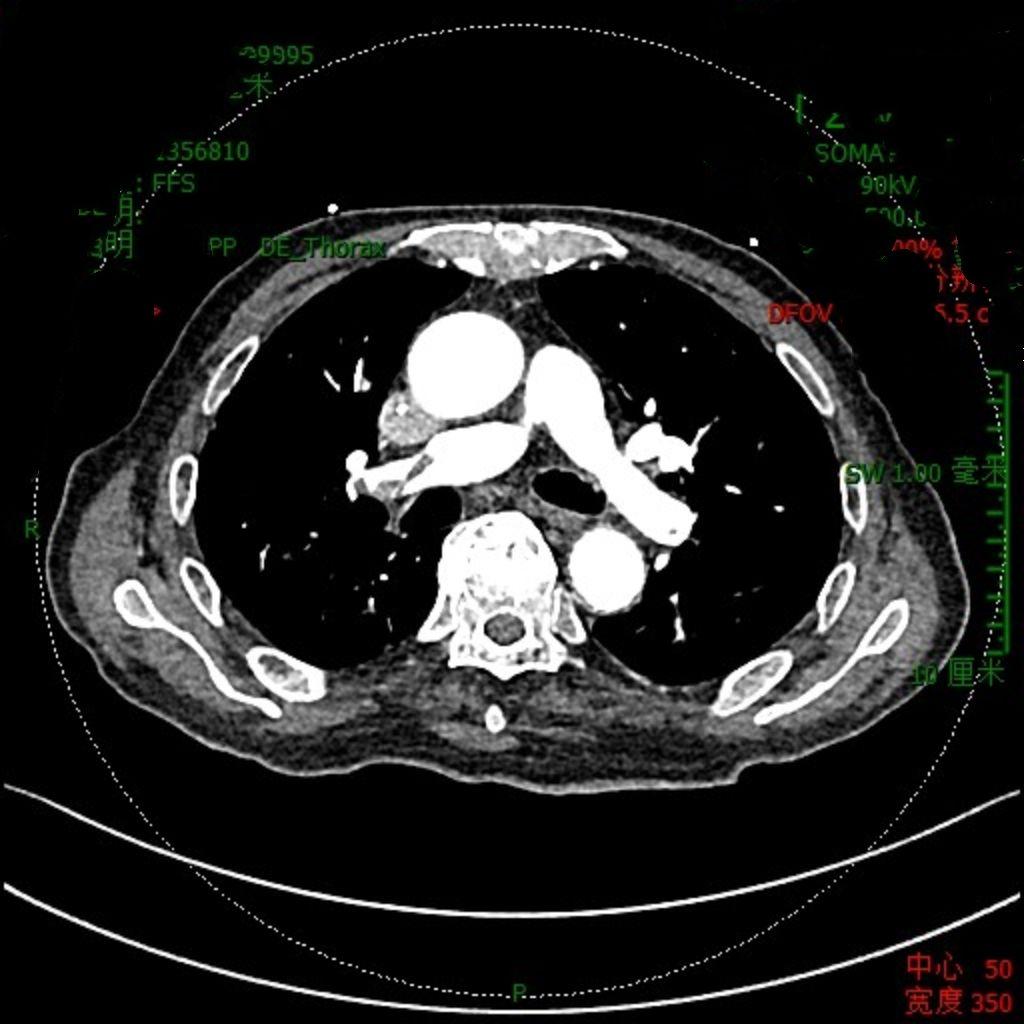

肺栓塞是血液肿瘤治疗中必须警惕的